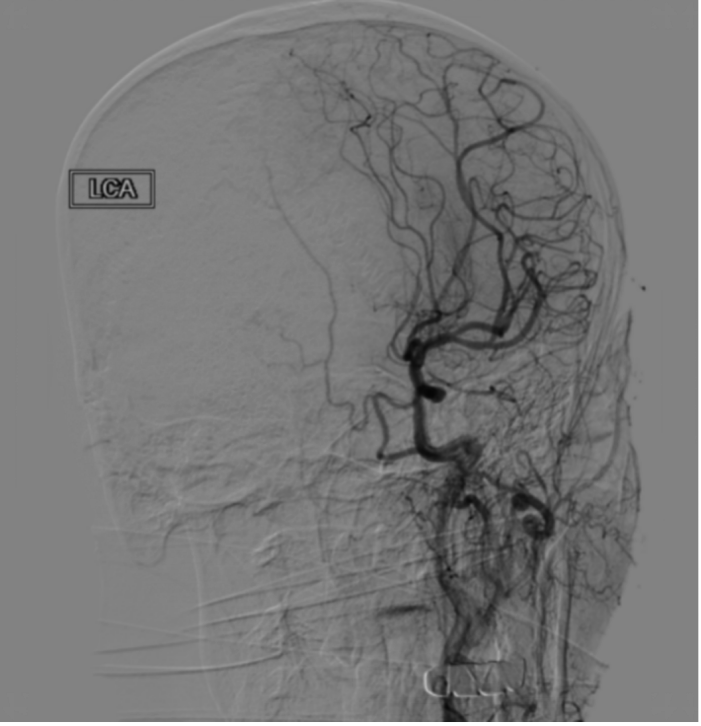

为明确脑梗死的责任血管和梗死周围脑组织血流灌注情况,医生给患者进一步完善了一站式多模CT检查,发现患者左侧大脑中动脉闭塞,左侧大脑半球广泛低灌注。随后神经介入团队立即行动,决定进行急诊介入取栓手术。在这场与时间的较量中,多学科协作无缝对接,从急诊接诊到手术台准备介入取栓,每一步都紧密相连。

幸运的是,溶栓治疗卓有成效,上台后造影显示患者大血管已完全溶通,患者病情迅速得到有效控制,他的右侧肢体逐渐恢复力量,言语也变得清晰。